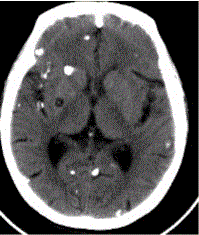

问题 患者男,45岁。头痛、癫痫10余年。查体:无发热,双侧肢体肌力正常。脑电图示双侧额颞叶棘波放电。CT表现如下图。 脑囊虫病的病理演变分为

选项 A.急性期 B.囊胞期 C.胶样囊胞期 D.肉芽肿结节期 E.结节钙化期 F.慢性期

答案 BCDE